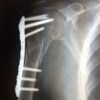

Операции на плечевой кости выполняются для всех типов переломов в случае, если костные отломки не могут быть сопоставлены и / или сохранены в нормальном положении с помощью средств закрытой фиксации. Обычно вмешательства выполняются в плановом порядке. Экстренные операции показаны при повреждении магистральных сосудов, прогрессирующем сдавливании лучевого нерва. Способ фиксации отломков зависит от типа и уровня перелома; обычные, Т-образные и угловые пластины, шпильки, шурупы, спицы, проволока. Иногда в послеоперационном периоде проводят иммобилизацию. Время восстановления составляет от 1,5 до 2,5 месяцев.

Переломы проксимального отдела плечевой кости (головы и шеи плеча) чаще встречаются у пожилых пациентов. Возраст и сопутствующие заболевания пациентов требуют особенно осторожного подхода при принятии решения об операции. Возможна угроза некроза головы при высоких переломах. Для закрепления фрагментов использовались иголки, губчатые винты, проволочные и Т-образные пластины. После остеосинтеза плечевой кости руку помещают на подушку в положении отведения. Активные и пассивные движения начинаются через 4-6 дней после операции. Швы снимаются через 10-14 дней. Контрольная рентгенография проводится сразу после вмешательства, через 10-14 дней (до выписки) и через 3-4 недели. Полная загрузка разрешается через 6-8 недель. Металлоконструкции снимаются через 6-12 месяцев.

Как правило, пластины и гвозди внутри костей используются для прикрепления фрагментов, реже проволоки. После операции рука помещается на подушку в положении отведения. Активные и пассивные движения начинаются с первого дня. Швы снимаются на 10-12 дней. Рентгенограммы плеча выполняются после операции, перед выпиской и позже каждую неделю, пока не появятся четкие признаки слияния. Полная загрузка разрешается через 8-10 недель. После удаления металлических конструкций возникает риск повреждения лучевого нерва, поэтому фиксаторы снимаются только в особых случаях (нагноение, появление аллергических реакций на имплантат).

В случае переломов дистальной части плечевой кости очень важно точно восстановить форму поверхности сустава, чтобы сохранить диапазон движений в локтевом суставе. Для закрепления фрагментов используйте спицы, крепежные винты и специальные пластины. Физиотерапию назначают с первого дня после операции. Швы снимаются на 10-12 дней. Полная загрузка разрешается через 6-8 недель. Имплантаты удаляются через 6-12 месяцев.